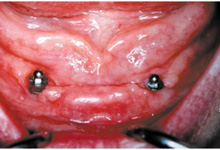

Kulové attachmenty

Kulové attachmenty

Bezzubá čelist je hlavní indikací pro ošetření pomocí implantátů. Zejména celkové zubní náhrady v dolní čelisti mají velice nízkou stabilitu a držení díky velkému úbytku kosti.

S pomocí zubních implantátů můžeme díky různým kotevním systémům (třmeny, kulové hlavy, Locatory) zajistit stabilitu a držení protézy nebo při použití většího počtu implantátů zhotovit pevné náhrady – můstky nalepené nebo našroubované na pevno na implantáty.

S těmito typy náhrad můžeme dosáhnout perfektní funkci, výbornou estetiku, fonetiku a současně zajistit u pacienta možnost dobré hygienickou péče a čištění, která je pro životnost implantátů velice důležitá.